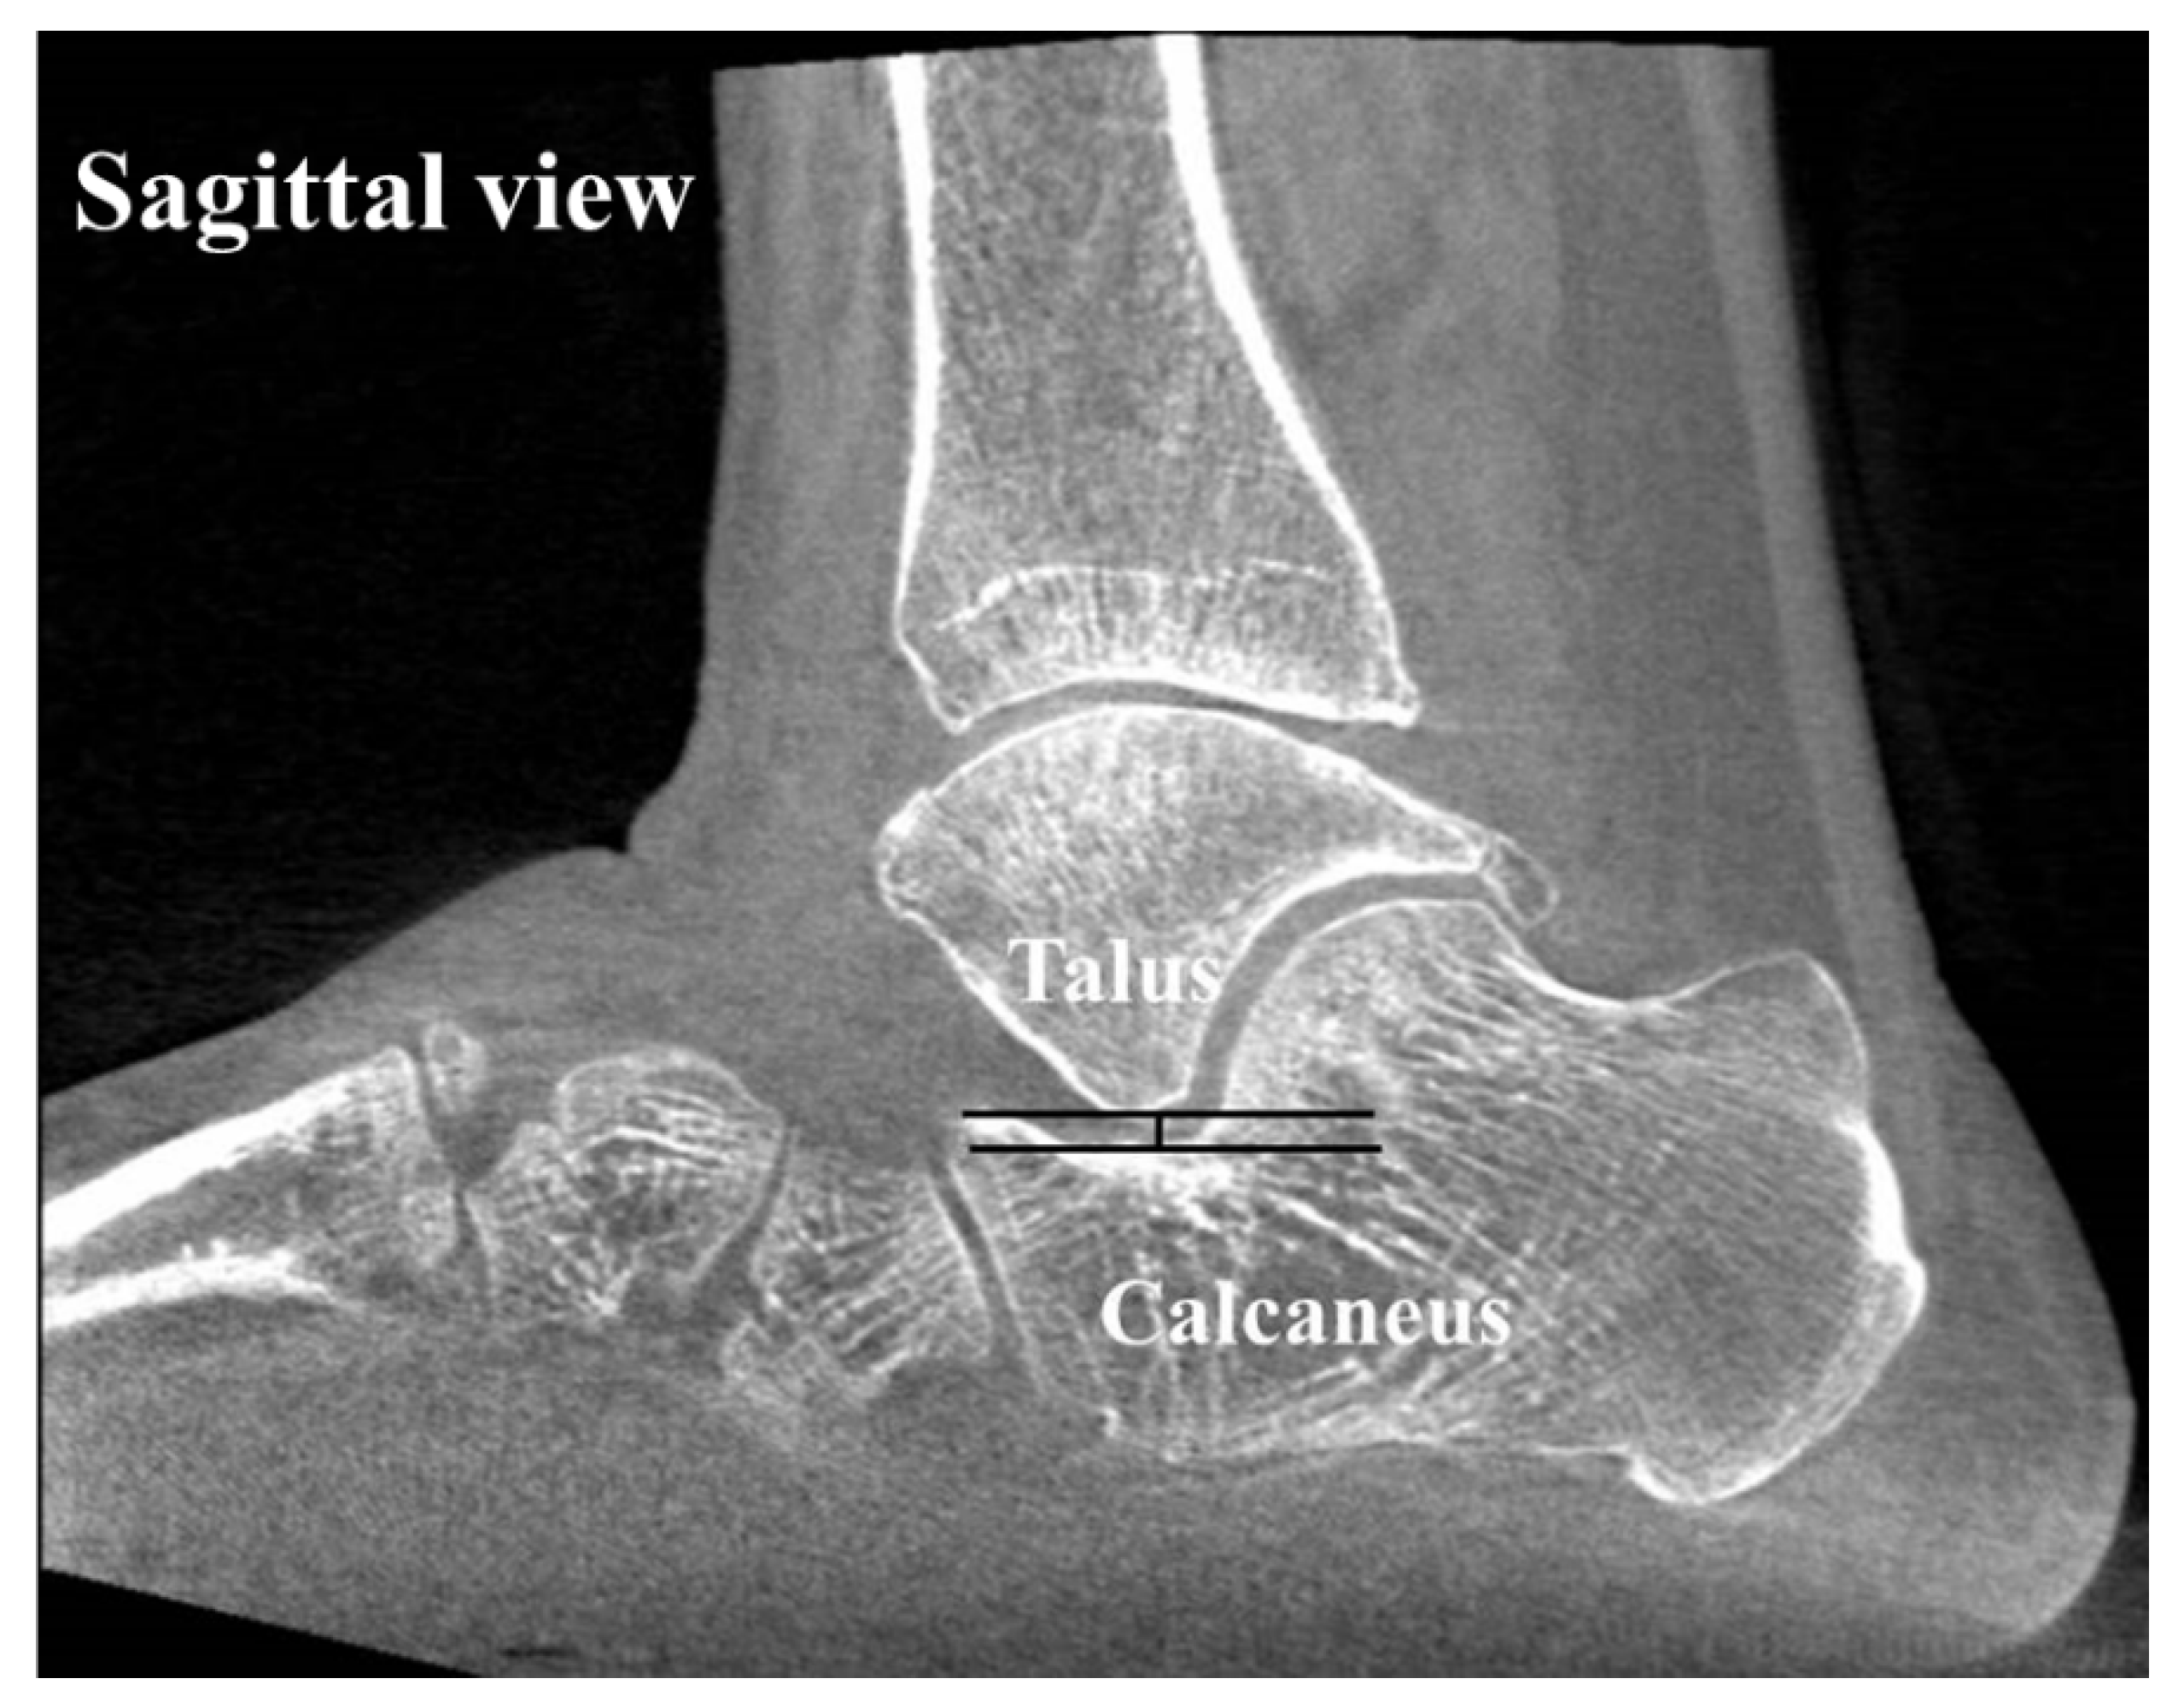

To assess the alignment of the hindfoot, including the subtalar joint on CT, four measurements which have been used in previous studies [1,22,23,24,25] were used: (1) the heel valgus angle (HVA), (2) the talocalcaneal distance (TCD) at the Gissane angle, (3) the subtalar joint subluxation (SL) and (4) the calcaneofibular distance (CF). Axial, sagittal and coronal (reconstruction thickness of 2 mm) bone window reformations of axial images were used for measurements. The heel valgus angle (HVA) was based on the axis of the distal tibial defined by a perpendicular line to the distal tibia joint surface and a line parallel the medial osseous contour of the calcaneus on the most posterior image, including the tibia and calcaneus (Figure 3). Axis of the distal tibia was defined using the most central coronal image through the distal tibial shaft. This image was identified as the one in which the tibial shaft diameter was maximal, and the tibial cortex was sharply defined. The talocalcaneal distance (TCD) at the Gissane angle was assessed measuring the shortest distance from the most inferior aspect of lateral talus process to the floor of the calcaneus in the sinus tarsi. This measurement was seen on sagittal images (Figure 4). The subtalar joint subluxation (SL) and the calcaneofibular distance (CF) were measured in the coronal plane at the level of the most posterior aspect of the fibula (Figure 5). The subtalar joint subluxation (SL) was measured from the lateral margin of the calcaneal articular surface to the lateral margin of the talar articular surface. The calcaneofibular distance (CF) was measured from the lateral margin of the calcaneal wall surface to the medial margin of the fibular articular surface.

Figure 4. The sagittal image of the foot shows the measurement for the talocalcaneal distance at the Gissane angle. Measurement was assessed as the shortest distance from the most inferior aspect of lateral talus process to the floor of the calcaneus in the sinus tarsi.